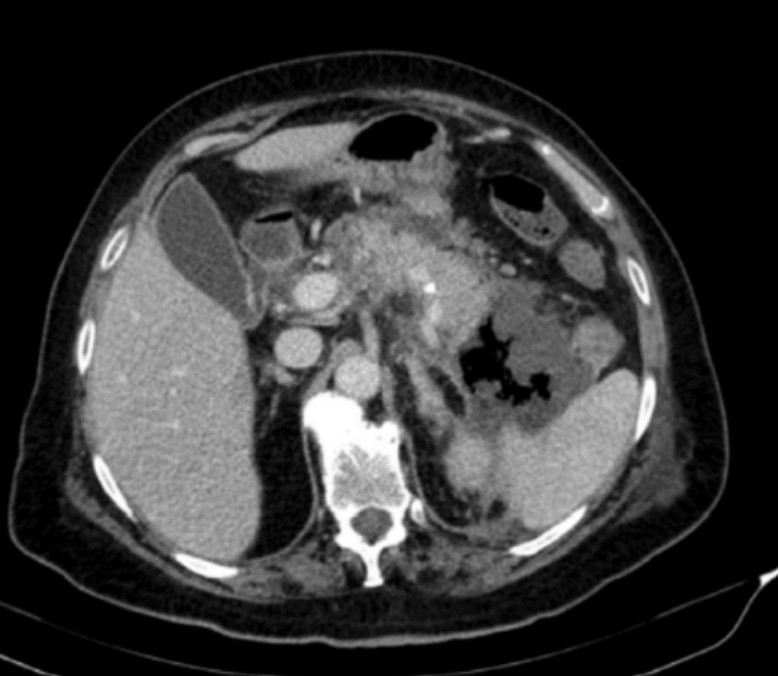

Abdominal pain

A 65-year-old man presents with central abdominal pain radiating to the back, associated with nausea and vomiting. He appears unwell. …